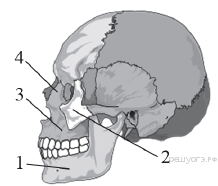

Какой цифрой обозначена скуловая кость черепа человека?

Варианты ответов

- 1

- 2

- 3

- 4